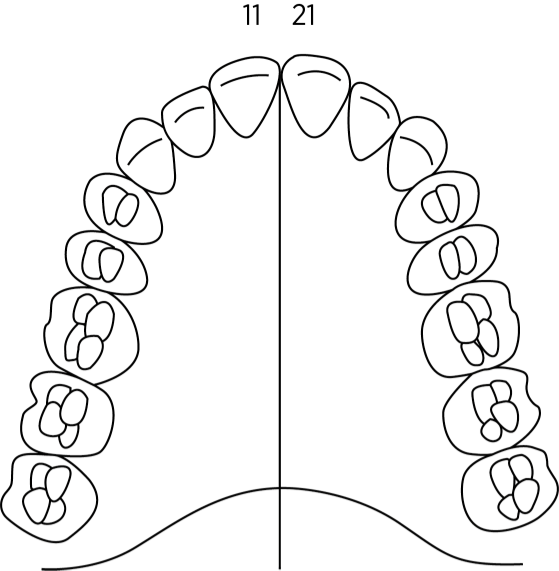

Vid välgrundad misstanke om cancerdiagnos remitterar onkologansvarig ÖNH-läkare patienten till käkkirurgiska kliniken för bedömning av tandstatus. Patienten utreds omgående kliniskt och radiologiskt inför MDK. Den radiologiska undersökningen består av helstatus och vid behov panoramabild. I vissa fall utreds patienten vidare med andra radiologiska tekniker.

Journalen ska innehålla uppgifter om anamnes, munhålestatus inklusive radiologiskt helstatus och vid behov panoramabild. För tandlösa patienter krävs endast panoramabild med kompletterande intraorala bilder av käkarnas frontparti, om inte annan patologi inom käkarna konstaterats som dokumenterats med annan radiologisk teknik.